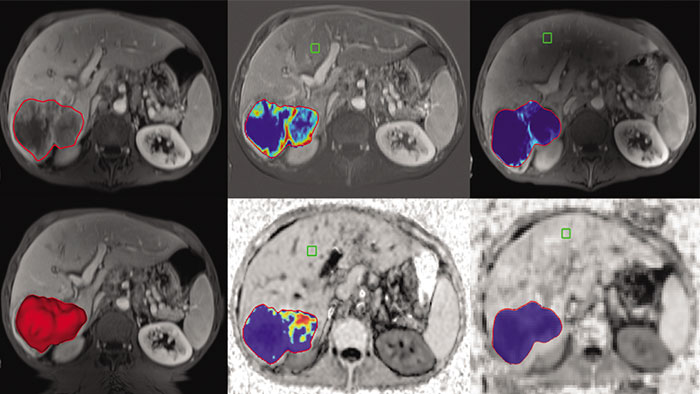

Semi-automatic tumor quantification

This semi-automated 3D (Volumetric) tumor response assessment tool, based on EASL (European Association for the Study of the Liver) criteria incorporates functional information from contrast-enhanced scans.

Advanced Liver segmentation

Automatically identifies, segments and quantifies the liver from the portal venous phase of a tri-phase liver scan and classifies the hepatic and portal veins.